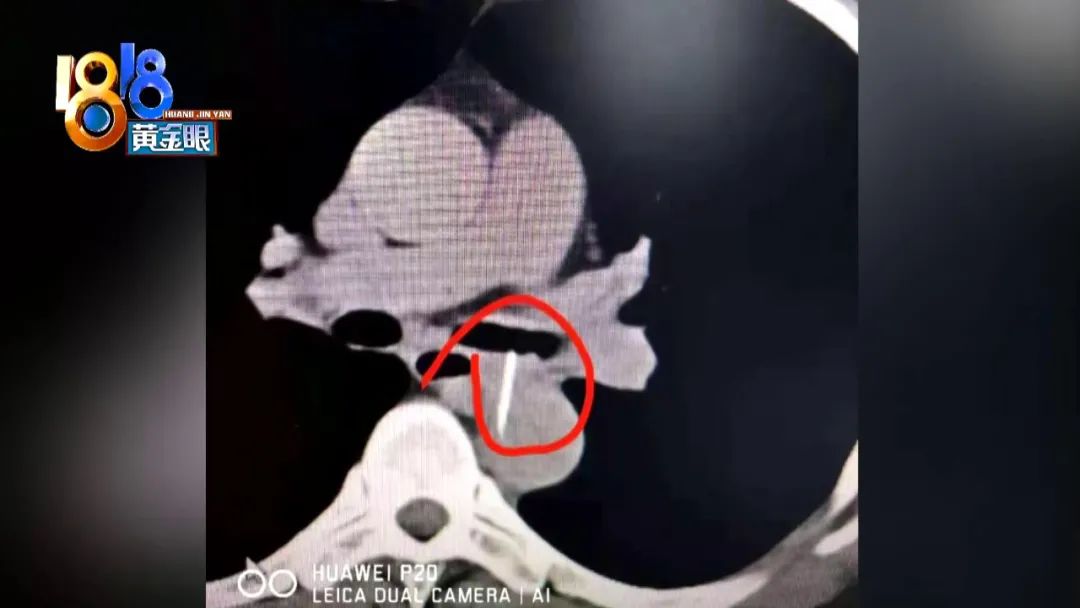

楊師傅住在浙江紹興,一個(gè)多月前,他出現(xiàn)了反復(fù)咳嗽,最近甚至開始咳血,這才去了醫(yī)院。醫(yī)生檢查發(fā)現(xiàn),他的情況十分兇險(xiǎn)。 從紹興當(dāng)?shù)蒯t(yī)院提供的片子看,楊師傅左支氣管里有異物。考慮到他有吃魚的習(xí)慣,一開始,醫(yī)生懷疑這是一根魚刺。4月26號(hào),楊師傅被轉(zhuǎn)到浙大邵逸夫醫(yī)院,他表面上看起來沒什么異樣,結(jié)果在診室里又突然開始咳血。 浙大邵逸夫醫(yī)院心臟外科副主任醫(yī)師 于長(zhǎng)江:“因?yàn)槲覀儗?duì)這個(gè)異物進(jìn)行測(cè)量,包括密度的評(píng)估,感覺像是金屬的,因?yàn)榛颊咄耆珱]有提供病史,說這個(gè)東西是怎么來的! 浙大邵逸夫醫(yī)院呼吸與危重醫(yī)學(xué)科主任 陳恩國(guó):“其實(shí)跟放射介入科的技師在說,我在外面嘀咕,我說這個(gè)好像不太像魚刺,太直了,因?yàn)轸~刺總會(huì)有點(diǎn)彎。” 后來,醫(yī)院采用支氣管鏡介入,清理掉氣道里大量的血塊凝結(jié),異物慢慢地露出了原貌,大家都嚇了一跳,竟然是一根針。 浙大邵逸夫醫(yī)院 呼吸與危重醫(yī)學(xué)科主任 陳恩國(guó):“其實(shí)就看出亮閃閃的,那時(shí)候大家說這應(yīng)該不是魚刺,不管怎么樣你還是要取出來,因?yàn)樗褚粋(gè)扁擔(dān)一樣橫在那里,所以你要直接拎是拎不動(dòng)的! 當(dāng)時(shí)這根針已經(jīng)刺穿楊師傅的胸降主動(dòng)脈和左支氣管,隨時(shí)有大出血的危險(xiǎn),嚴(yán)重的會(huì)導(dǎo)致休克,甚至是死亡。最保守的取針方式,是通過開胸手術(shù),這能讓所有風(fēng)險(xiǎn)都看得見,但如果這樣做,給患者帶來的創(chuàng)傷將非常大。經(jīng)過多學(xué)科研討,最后醫(yī)院從楊師傅的口腔介入,分四次取出異物。 浙大邵逸夫醫(yī)院呼吸與危重醫(yī)學(xué)科主任 陳恩國(guó):“所以我們只能把它斷掉,拔出來一點(diǎn),斷掉 拔出來一點(diǎn),最后一下子就可以把它拎出來,拔出來過程就怕出血。我大學(xué)同學(xué)是做胸外科的,他說你膽子真大,我說這種病人到你手上怎么辦?他說肯定開胸啊,把整個(gè)胸腔打開,暴露得很清楚。像我們來說,就是我相信我們的胸外科醫(yī)生,他放了支架以后,像我們打針的時(shí)候,拔針一樣的,拔好一針,馬上就按住! 手術(shù)持續(xù)了兩個(gè)小時(shí),取出的這根針長(zhǎng)3.6厘米。 事后,楊師傅的家屬突然想起來,在今年2月份,楊師傅背部有輕微的刺痛感,當(dāng)時(shí)還拍了照片,因?yàn)闂顜煾的菚?huì)兒剛好發(fā)帶狀皰疹,所以一直沒有在意。至于這根針是哪里來?楊師傅說,他是開工程車的,經(jīng)常睡在工地上。 楊師傅:“后來到我們那的地方醫(yī)院,看了一下,他說看不出來,什么東西,好像一個(gè)蟲子咬過一樣,回來的時(shí)候,感覺很胸悶,很痛! 浙大邵逸夫醫(yī)院心臟外科副主任醫(yī)師 于長(zhǎng)江:“就是脊柱稍微靠左側(cè)一點(diǎn),其實(shí)這側(cè)肌肉里面就是胸腔,胸腔后面就是降主動(dòng)脈,其實(shí)先穿過降主動(dòng)脈內(nèi)側(cè)壁,跟脊柱旁的夾角,然后過去了,再往前就是左主支氣管。肌肉收縮、呼吸運(yùn)動(dòng),因?yàn)獒樇馐窃谇懊,后面是鈍的,肌肉一推,前面阻力小! 手術(shù)后,楊師傅在重癥監(jiān)護(hù)室只待了兩天,沒有任何不良反應(yīng)。昨天,他正式出院了。